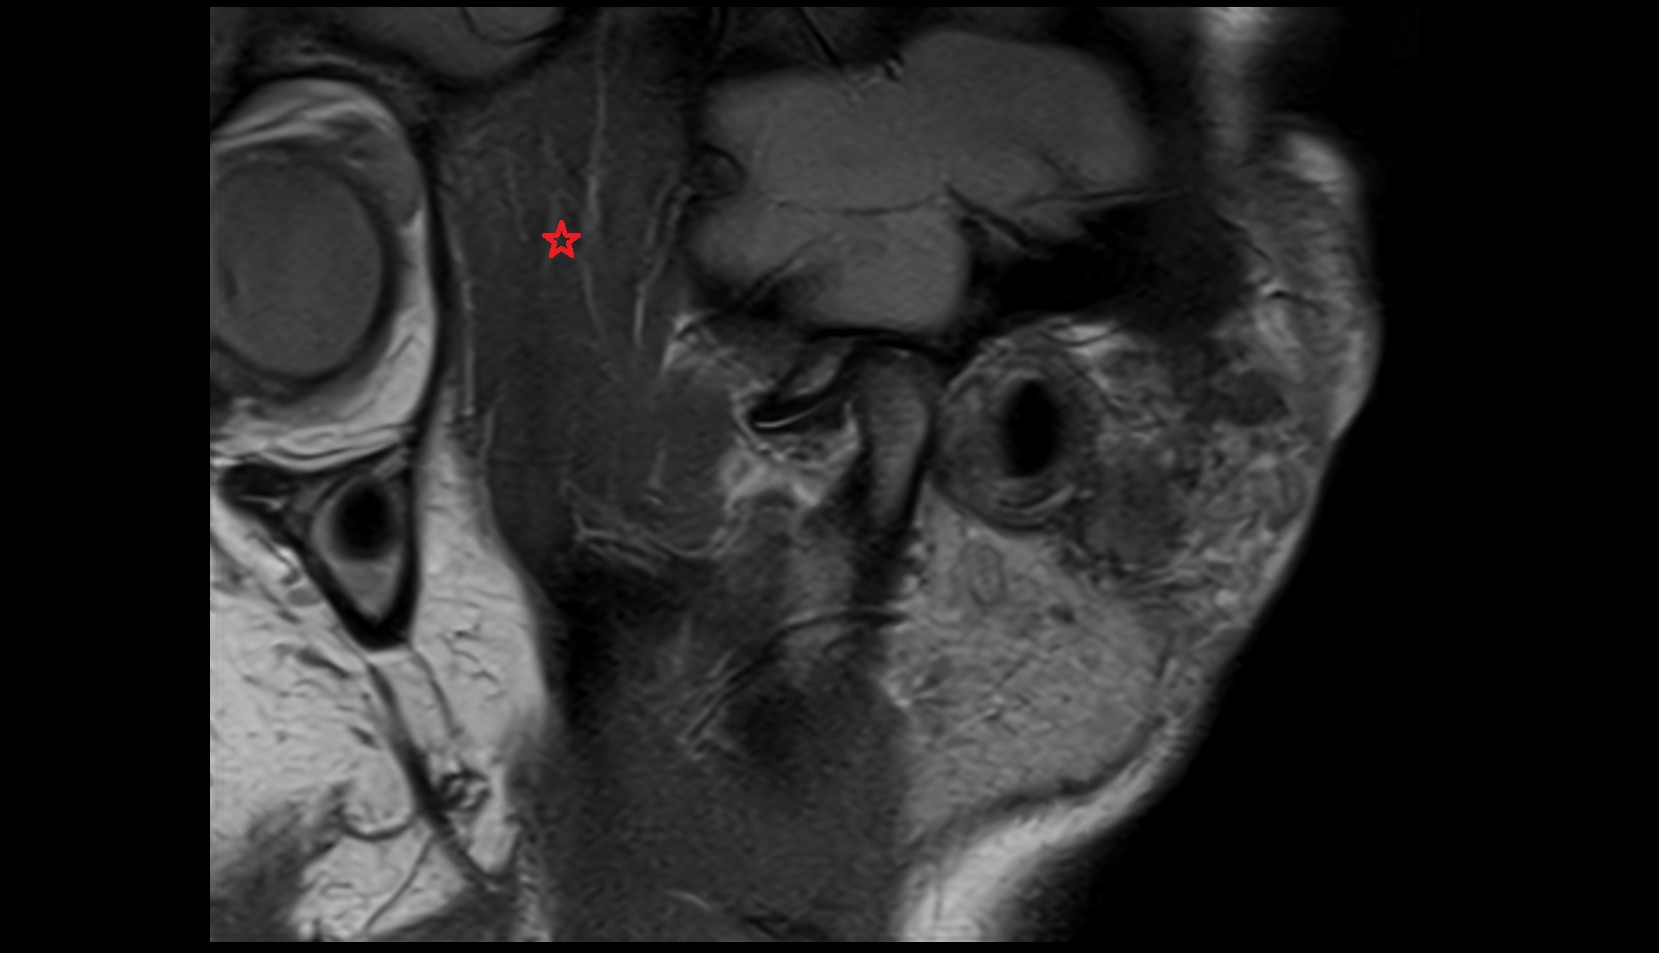

- Subarachnoid space of optic nerve